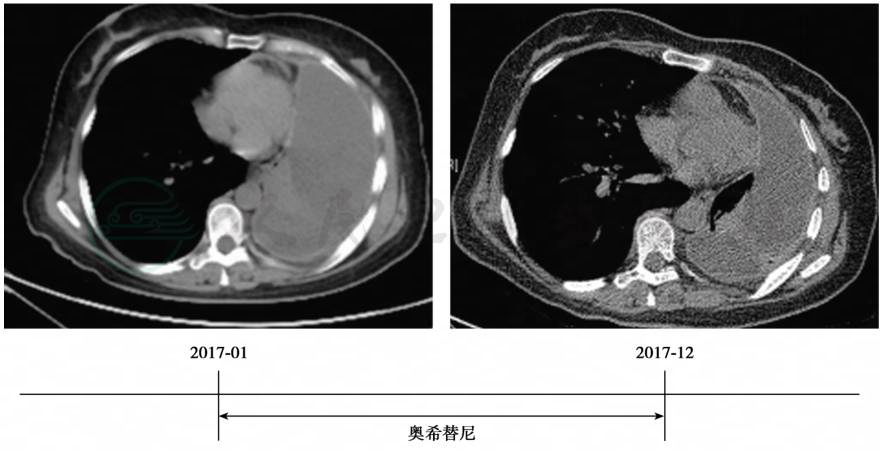

患者口服奥希替尼后,一般状况明显改善,无特殊不适主诉。PS评分1分,日常生活可以自理。2017年12月11日复查胸部CT示病情稳定(SD)(图2)。

图2 复查胸部CT提示:胸腔积液较前减少,病情基本稳定